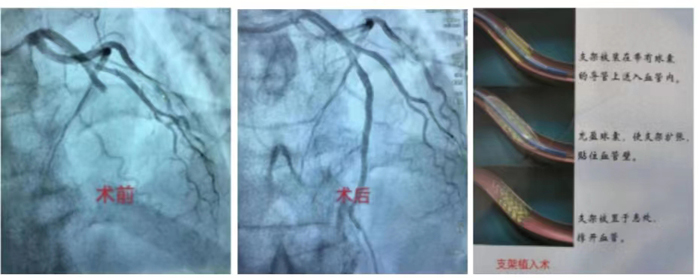

冠心病介入診療技術:科室常規開展冠狀動脈造影術、經皮冠狀動脈球囊擴張術(PTCA)、經皮冠狀動脈藥物球囊擴張術,振波球囊技術治療冠脈嚴重鈣化病變、冠狀動脈支架置入術、心臟血管內超聲檢查(IVUS)、血流儲備分數測定(FFR)、冠狀動脈旋磨成形術等介入手術。在冠脈左主干、分叉病變、慢性完全性堵塞性病變、彌漫性及鈣化病變等復雜病變方面積累了豐富的經驗。胸痛中心針對急性心肌梗死患者開通綠色通道,其中急診冠心病介入診療技術為棗莊地區開展最早,挽救急性心肌梗死病人最多的科室。

急診PCI術:是指在患者發生急性心肌梗塞后12小時內進行的冠狀動脈血運重建,患者首先在導管室行冠狀動脈造影術,找出冠狀動脈“罪犯”血管及其病變部位,對病變部位行經皮冠狀動脈腔內成形術和植入支架,使閉塞的血管得以再通,梗死相關心肌得以及早的再灌注和功能恢復。可以說,急診PCI術為挽救急性心梗垂危的生命在最短的時間內構建了一條綠色的通道,提高危重癥患者的搶救成功,使急性心肌梗死的死亡率下降,提高患者的生活質量。因此,在急性心肌梗死的時間窗內,介入治療已是首選治療手段,其急診PCI大大降低死亡率及心肌梗死并發癥,提高生存率及改善生活質量。